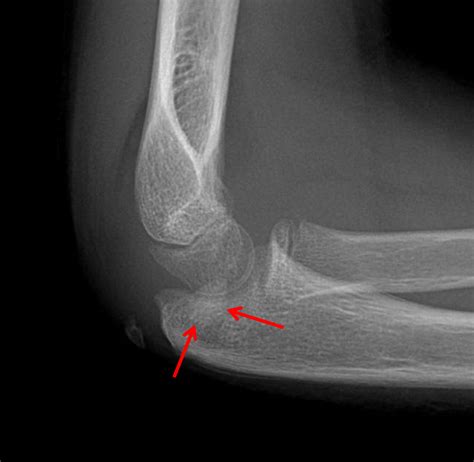

Diagnosing a Medial Epicondyle Fracture

Diagnosing a Medial Epicondyle Fracture involves a combination of physical examination and imaging tests. The diagnostic process typically includes:

• Physical Examination: The healthcare provider will assess the elbow for swelling, tenderness, and range of motion. They may also check for any deformities or instability in the joint.

• Imaging Tests: X-rays are the primary imaging tool used to diagnose a Medial Epicondyle Fracture. They can reveal the location and extent of the fracture. In some cases, additional imaging such as a CT scan or MRI may be required to provide a more detailed view of the injury.

Accurate diagnosis is crucial for determining the appropriate treatment plan.